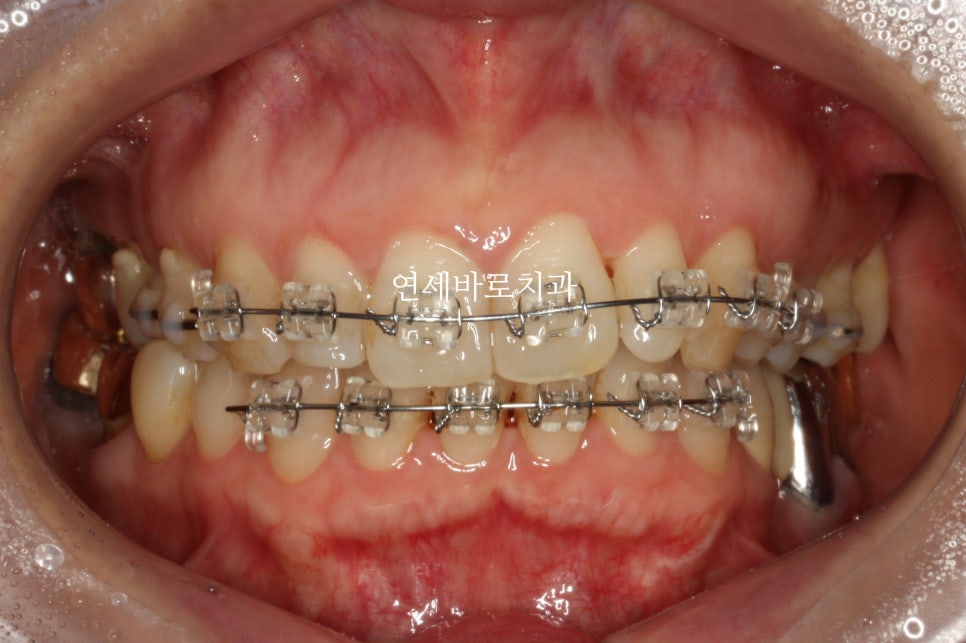

처음 치료를 시작한 날의 모습입니다.

아이가 하고 싶어한 만큼 당연히 열심히 잘 껴주었습니다.

이 환자분도 중심선을 맞추기 위해 고무줄을 함께 사용했습니다.